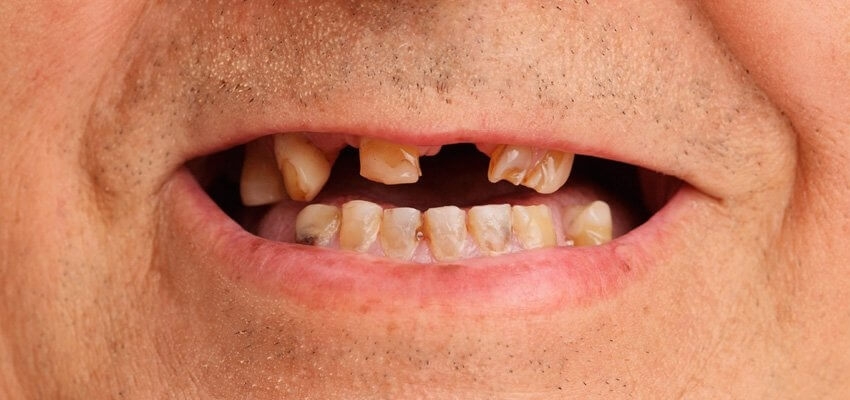

Consequência do refluxo na saúde bucal:

Erosão dentario devido à acidez do suco gastrointestinal, podemos afirmar que uma perda progressiva e irreversível da estrutura dental, tornando os dentes sensíveis a estímulos térmicos (frio, quente e ao ar ), táteis, amarelados, boca seca (xerostomia), devido à diminuição e quantidade do fluxo salivar, consequentemente aumento de aftas, doença periodontal e halitose. Normalmente, a procura por um cirurgião dentista é realizada após a evolução dos desgastes dentários provenientes da erosão, onde a necessidade de reabilitações mais invasivas, como tratamento endodônticos (canal), coroas, facetas, já estão indicadas para devolução da forma, textura e comprimento dos dentes como do terço inferior da face em casos mais avançados, do contrário a perda dentária será inevitável. O refluxo gastroesofágico tem tratamento. Caso sofra desse mal, procure o gastroenterologista para tratar o refluxo e um cirurgião dentista para tratar as consequênciais bucais. Afinal, não deixe que esse doença acabe com seu prazer de sorrir, falar e se apresentar.